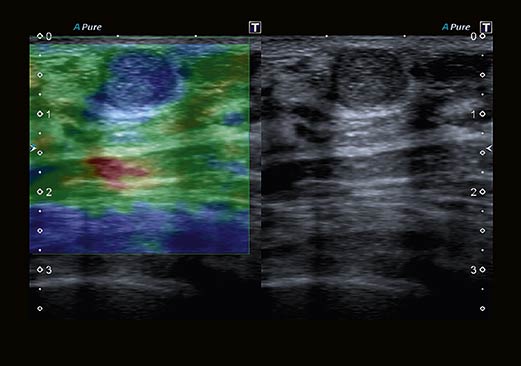

- Улучшенный динамический поток Advanced Dynamic Flow (ADF) – запатентованная технология Toshiba, обеспечивающая высокое разрешение при цветовом доплеровском сканировании.

- ApliPure – автоматически настраивает контрастность и удаляет шум с картинки на экране.

- Компрессионная эластография – классический метод раннего выявления опухолей.

- Эластография сдвиговой волны – новейший метод, позволяющий обнаружить опухоли при помощи определения скорости движения волн.

Технология ApliPureTM+ объединяет в себе преимущества функций пространственного и частотного совмещения. Позволяет получать изображения с высокой четкостью и детализацией с сохранением всех клинически значимых маркеров-артефактов.

Эластография в реальном времени. Наше комплексное решение для эластографии с функциональностью необработанных данных помогает локализовать и оценивать ощутимые массы с высокой точностью, чувствительностью и воспроизводимостью в широком диапазоне клинических условий. Различные параметры эластичности ткани могут быть определены количественно или иметь цветовую кодировку на параметрических изображениях, делая подозрительные изменения ткани количественными и видимыми на ультразвуковом изображении.

Индикатор качества помогает вам правильно подать давление на датчик, гарантируя, что вы всегда получаете надежные результаты.